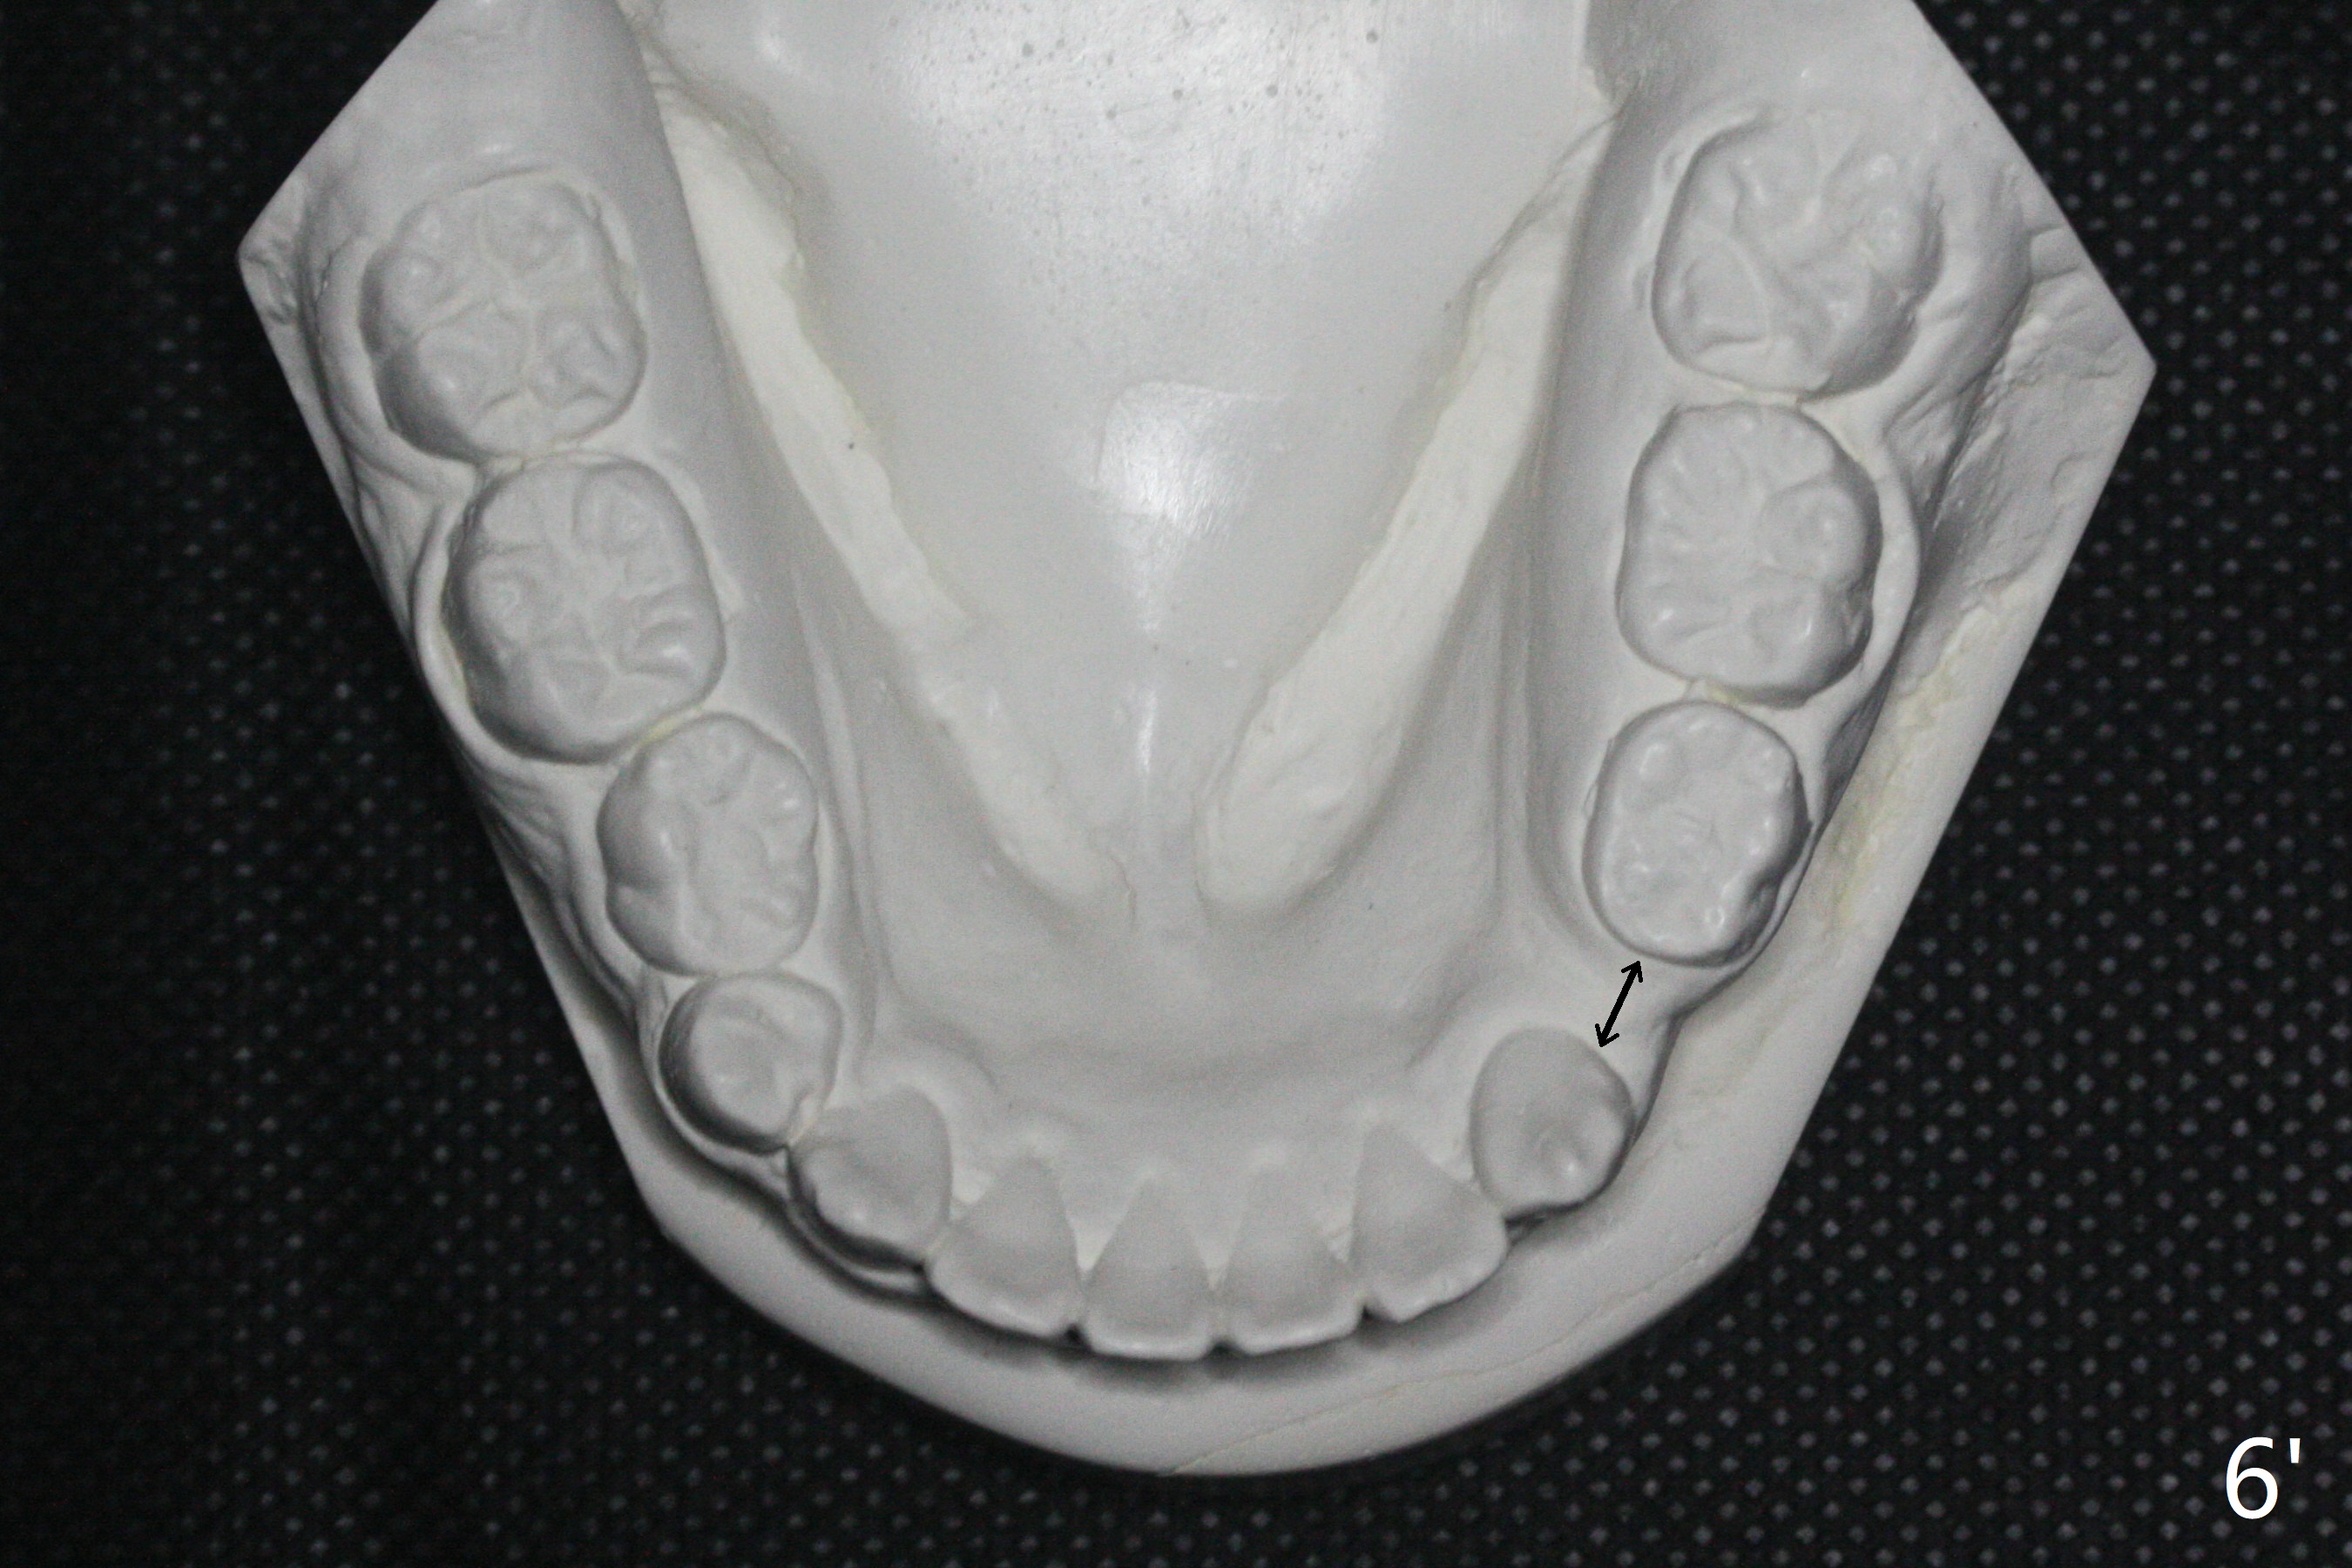

One-year-8-month orthodontic treatment reduces anterior overjet (Fig.1 (double arrows),1', with facial profile improvement), corrects right 1st molar cross bite (Fig.2,2') and dental midlines (Fig.3,3'), closes the diastema between UL3 and 4, extrudes UL5 (Fig.4,5,4',5'), and increases space for future implant at LL4 (Fig.6,6'). In fact large arches with distemata make the treatment possible! Extrusion of UL5 leads to root development (Fig.7, 7' (R)). The increased space at LL4 (Fig.7' *) appears insufficient for an implant.